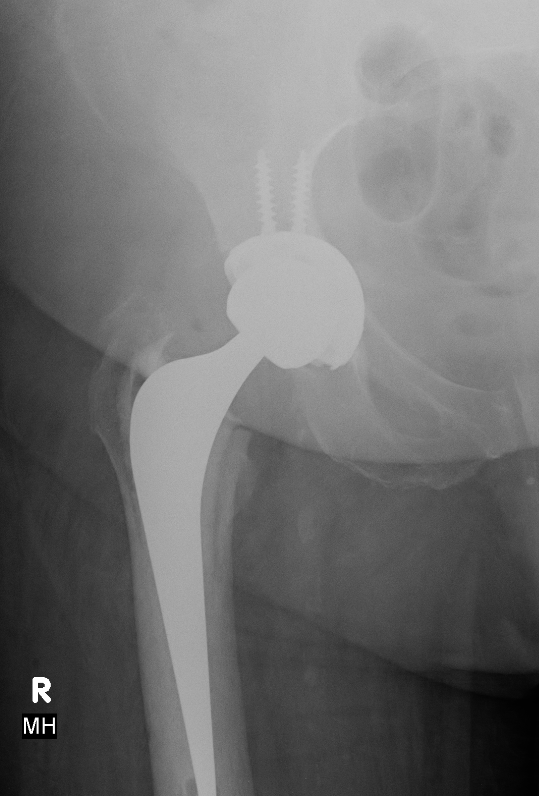

Postoperative acetabular fracture treated with double posterior plating